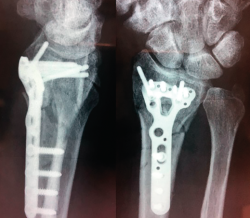

Figura 3. Ausencia de consolidación establecida, 6 meses de la fractura.

A los 6 meses no existió progreso radiológico y la falta de consolidación se manifestó claramente con pérdida de la reducción progresiva y dolor (Figura 3). En ese momento, se realizó la segunda cirugía abierta: extracción del material de síntesis que presentaba tornillos distales rotos (los bloqueados) y aflojados el resto, toma de muestras para cultivo, toma de muestra para anatomía patológica, limpieza del foco, perforación del hueso distal y proximal, colocación de autoinjerto tricortical estructural impactado y esponjosa de la cresta ilíaca y nueva síntesis con placa Acu-Loc 2® distal estándar larga de Acumed. Se consiguió restituir aceptablemente la longitud del radio respecto a la articulación radiocubital distal, quedando cierta traslación radial y extensión que provocaba una protrusión volar de la zona distal de la placa conformada. No se realizó intervención en la articulación radiocubital distal, ya que no presentaba ni inestabilidad ni dolor significativos, ni signos artrósicos francos.